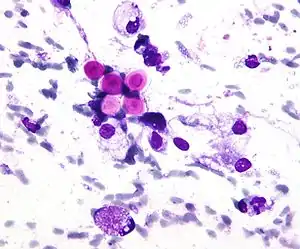

Diagnosis is by isolating Cryptococcus from a sample of affected tissue or direct observation of the fungus by using India ink staining of body fluids.[9] It can be cultured from a cerebrospinal fluid, sputum, and skin biopsy.[9] Treatment is with fluconazole or amphotericin B.[9][11]

Diagnosis

Any person who is found to have cryptococcosis at a site outside of the central nervous system (e.g., pulmonary cryptococcosis), a lumbar puncture is indicated to evaluate the cerebrospinal fluid (CSF) for evidence of cryptococcal meningitis, even if they do not have signs or symptoms of CNS disease. Detection of cryptococcal antigen (capsular material) by culture of CSF, sputum and urine provides definitive diagnosis.[27] Blood cultures may be positive in heavy infections. India ink of the CSF is a traditional microscopic method of diagnosis,[28] although the sensitivity is poor in early infection, and may miss 15–20% of patients with culture-positive cryptococcal meningitis.[29] Unusual morphological forms are rarely seen.[30] Cryptococcal antigen from cerebrospinal fluid is the best test for diagnosis of cryptococcal meningitis in terms of sensitivity.[31] Apart from conventional methods of detection like direct microscopy and culture, rapid diagnostic methods to detect cryptococcal antigen by latex agglutination test, lateral flow immunochromatographic assay (LFA), or enzyme immunoassay (EIA). A new cryptococcal antigen LFA was FDA approved in July 2011.[29][32] Polymerase chain reaction (PCR) has been used on tissue specimens.

Biopsy

A special stain may be needed to see the cryptococcus capsule.[33]